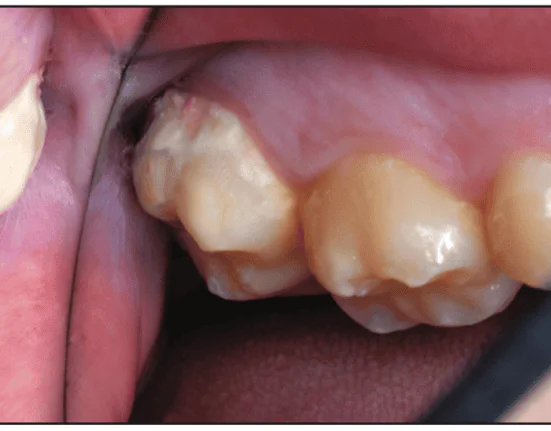

Figure 6. Second molar buccal surface decalcification in a 15-year-old patient.

smooth-surface dental caries

Figure 7. After local infiltration anes- thesia, a retraction cord was placed.